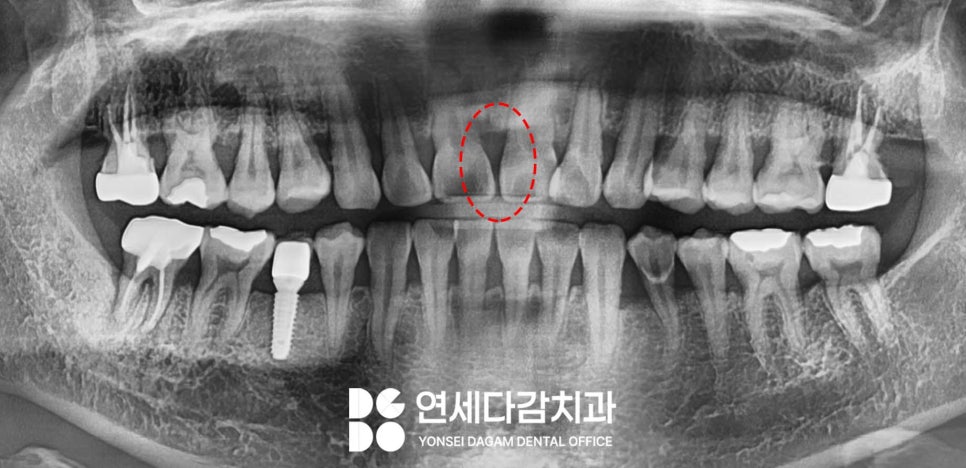

앞니 사이가 벌어져 있다면

어떤 치료를 선택 하시겠습니까?

앞니 사이가 벌어진 상태는

의학적으로 '치간이개(diastema)'

라고 부르는데,

이는 단순한 외관상의 문제가 아니라

때로는 기능적인 부분에도

영향을 미칠 수 있습니다.

특히 잘 보이는 곳이기 때문에

얼굴의 인상을 좌우하는

중요한 요소이기도 합니다.